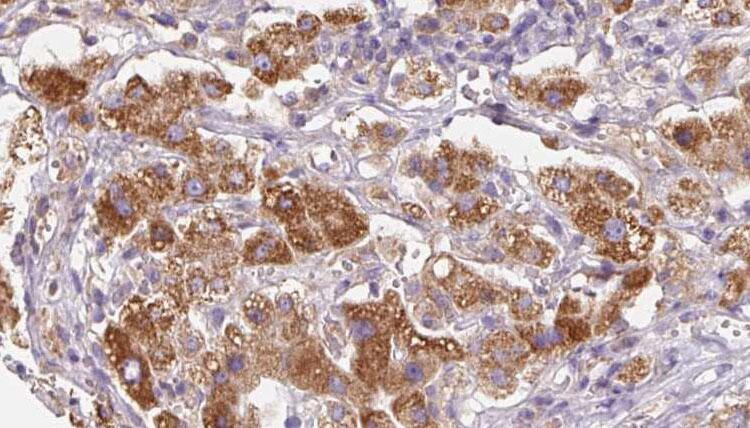

分类: 科研抗体货号: P42786别名: CIS3; SSI3; ATOD4; Cish3; SSI-3; SOCS-3应用: WB,IHC反应种属: Human,Mouse